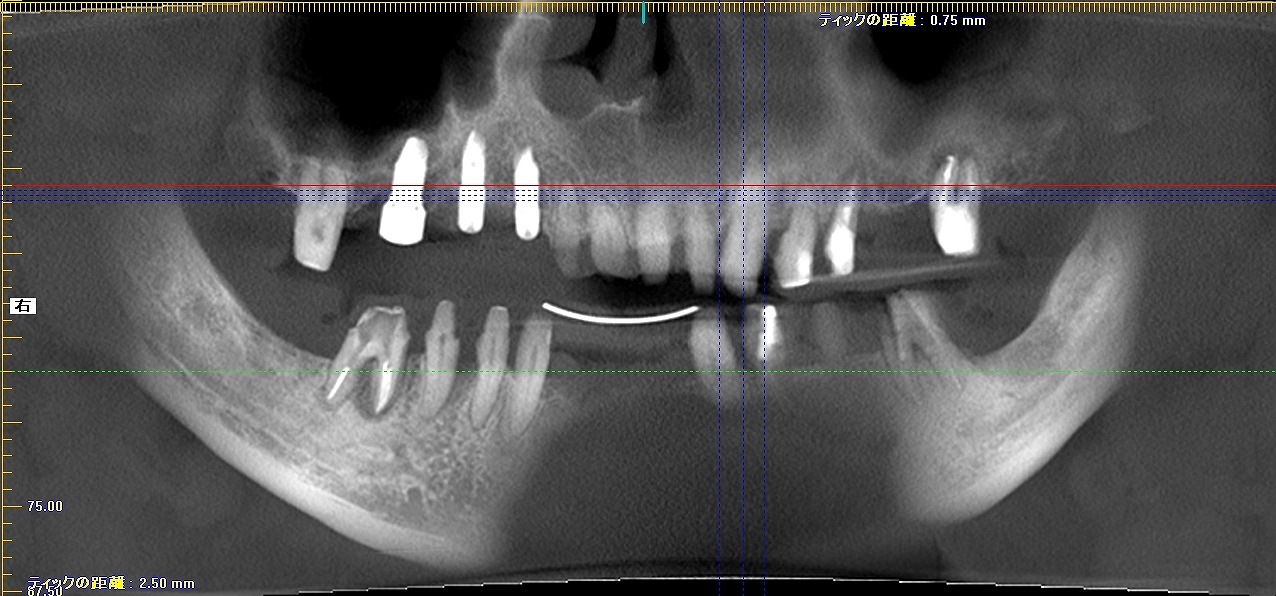

このように3本インプラントを埋入を行っています

インプラントが3か月もすれば固まり、仮歯にて咬合を再構成して

いきます

仮歯の状態になります